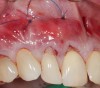

Fig 9. Two years postoperative. A complete root coverage and increase of the zone of attached and keratinized tissue is observed.

Figure 9

Fig 10. Cross-sectional view of the preoperative and postoperative (2 years). A three-dimensional increase of zone of keratinized and attached tissue is observed, restoring the lost attachment apparatus and correcting the gingival deformity in height and width.

Figure 10

Fig 11. Cross-sectional view of the preoperative and postoperative (2 years). A three-dimensional increase of zone of keratinized and attached tissue is observed, restoring the lost attachment apparatus and correcting the gingival deformity in height and width.

FIgure 11